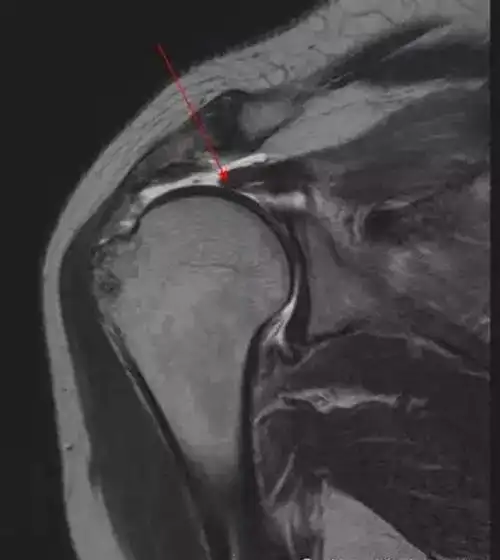

肩关节肌腱病一文读懂肩袖损伤的磁共振分级